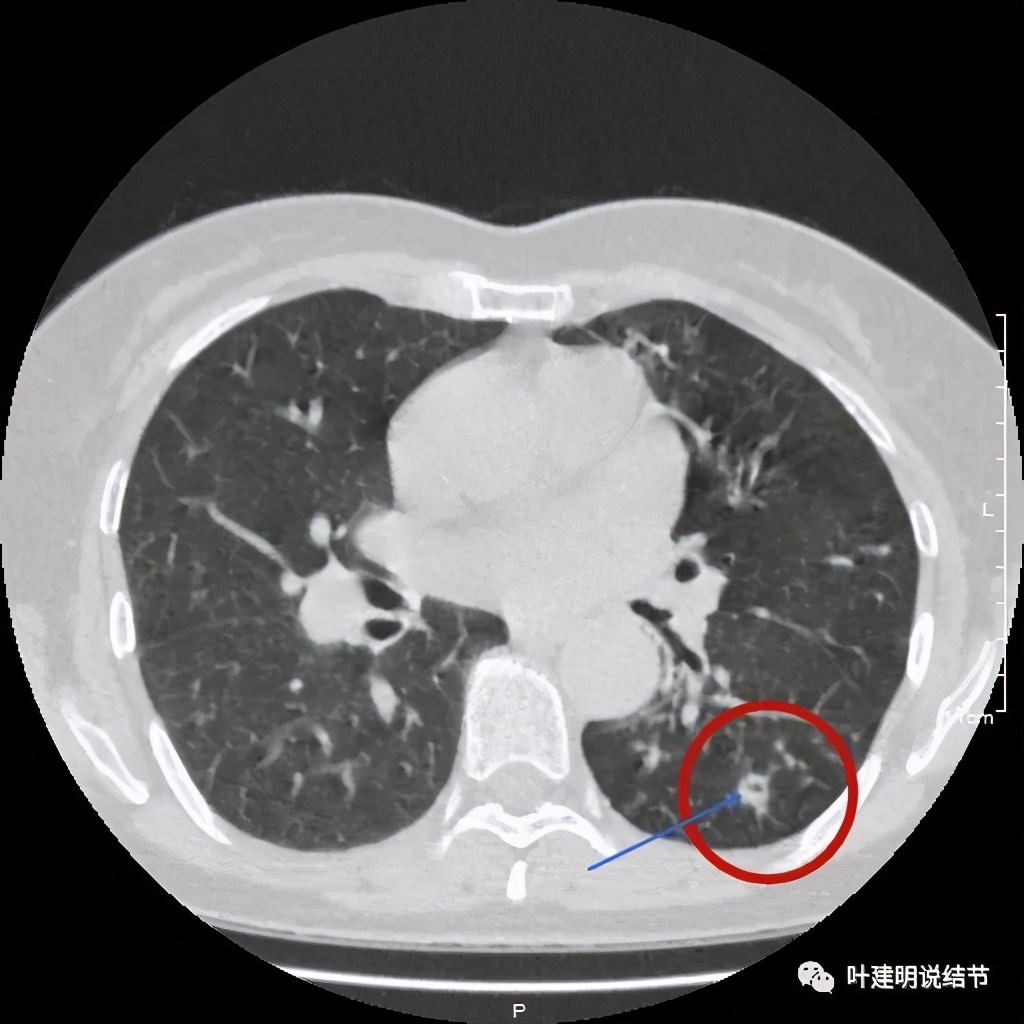

上图见病灶边上有血管

上图示病灶血管征较明显,有微小血管从不同方向走向病灶